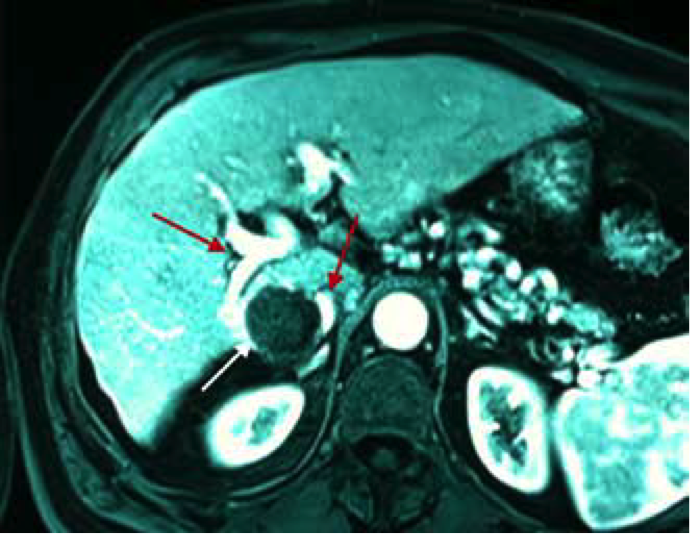

Un paziente con lesione epatica (freccia bianca in Figura), parzialmente esofitica, posizionata tra un ramo della vena porta e la vena cava, è stato sottoposto a Termoablazione con EchoLaser, utilizzando 4 fibre due posizionate nella parte superiore della vena porta e due nella parte inferiore. La lesione, particolarmente difficile da trattare per gli elementi vascolari che la circondano, è stata ablata completamente senza alterazione delle strutture vascolari circostanti.

Immagine RM ad 1 mese dal trattamento che mostra una completa ablazione (freccia bianca)

Immagini per gentile concessione del Dott. Giovan Giuseppe Di Costanzo (Ospedale Cardarelli, Napoli)